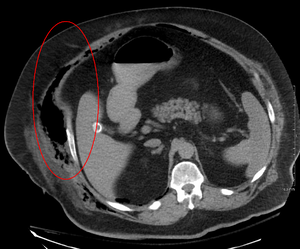

التصوير المقطعي المحوسب (الأشعة المقطعية) على وشك الكشف عن حوالي 80٪ من الحالات بينما قد يتمكن التصوير بالرنين المغناطيسي من الالتقاط أكثر قليلا..[2]

يلعب التصوير دورًا محدودًا في تشخيص التهاب اللفافة الناخر. يعد التأخير الزمني في إجراء التصوير مصدر قلق كبير. قد يُظهر التصوير الشعاعي البسيط انتفاخ الرئة تحت الجلد (غاز في النسيج تحت الجلد)، وهو ما يوحي بشدة بحدوث تغيرات نخرية، ولكنه ليس حساسًا بدرجة كافية لاكتشاف جميع الحالات، لأن التهابات الجلد الناخر التي تسببها بكتيريا المطثية غير المعدية عادة لا تظهر انتفاخ تحت الجلد. إذا كان التشخيص لا يزال موضع شك، فإن التصوير المقطعي المحوسب (CT) والتصوير بالرنين المغناطيسي (MRI) هما الأكثر حساسية من التصوير الشعاعي العادي. ومع ذلك، فإن كلا من الأشعة المقطعية والتصوير بالرنين المغناطيسي ليست حساسة بما يكفي لاستبعاد التغييرات الناخر تماماً.[2] قد يُظهر الفحص بالأشعة المقطعية سماكة اللفافة، وذمة، وغازات تحت الجلد، وتكون خراج.[2] في التصوير بالرنين المغناطيسي، عندما يحدث تجمع السوائل مع وجود التهاب ناخر، أو زيادة السماكة أو التحسين باستخدام حقن التباين، يجب الاشتباه بشدة إلى وجود التهاب اللفافة الناخر. وفي الوقت نفسه، يمكن أن يُظهر التصوير بتخطيط الصدى تكوين خراج سطحي، ولكنه ليس حساسًا بدرجة كافية لتشخيص التهاب اللفافة الناخر.[2] يمكن لفحص التصوير المقطعي المحوسب اكتشاف حوالي 80٪ من الحالات، بينما قد يلتقط التصوير بالرنين المغناطيسي أكثر قليلاً.[12]